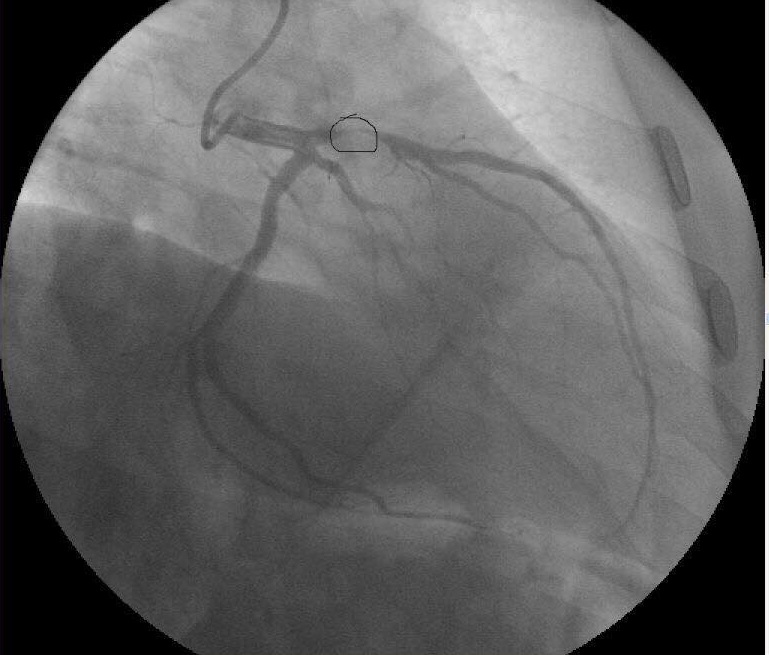

– Після інфаркту на мене дивилися, як на відпрацьований матеріал, – пригадує чоловік і демонструє знімок коронографії, зроблений 7 років тому. На ньому перекрита тромбом судина. Каже: якби не ота світла ниточка, просвіт у 5% кровотоку, він би сьогодні про усе це не розповідав.